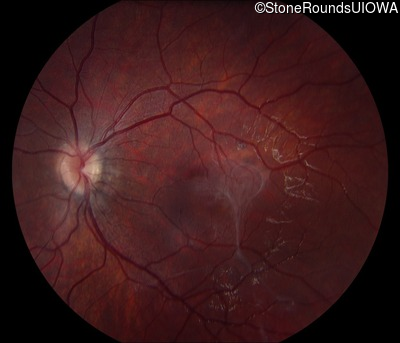

This 9 year old male was noted to have some crossing of his eyes at 2 months of age and the eye exam which followed identified a retinal lesion in the right eye. When he was six years old an epiretinal membrane was noted in his left eye. Two years later it was decided that it was a thin hamartoma in that eye as well. He underwent neuroimaging at age 7 which identified bilateral acoustic neuromas.

| Age at visit: 7 years |

| Age at visit: 8 years |

| Age at visit: 10 years |